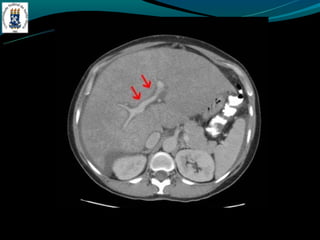

GÁS NO SISTEMA PORTA

-Mais frequentemente associado:

-Isquemia intestinal nos adultos

-Enterocolite necrosante nos RN

-Outras causas: colonoscopia recente, sonda de gastrostomia, DII,

diveticulite, abscesso abdominal…

GÁS NO SISTEMAPORTA -Mais frequentemente associado: -Isquemia intestinal nos adultos -Enterocolite necrosante nos RN -Outras causas: colonoscopia recente, sonda de gastrostomia, DII, diveticulite, abscesso abdominal…